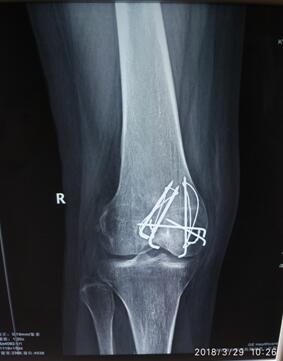

患者术前膝关节正侧位X线

孙主任通过查体和观看膝关节X线,得出患者是膝关节骨折术后关节僵硬,可以关节镜下微创松解治疗。住院医师申福国做术前查体,发现患者右侧膝关节伸约0°,屈曲约32°,几乎为完全僵硬关节,孙主任组织科内微创治疗小组进行病例讨论,对患者术中手术方案及术后康复治疗均做出完整规划。